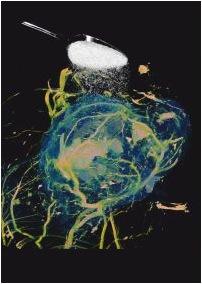

A new technique for detecting cancer by imaging the consumption of sugar with magnetic resonance imaging (MRI) has been unveiled by University College London (UCL) scientists. The breakthrough could provide a safer and simpler alternative to standard radioactive techniques and enable radiologists to image tumors in greater detail.